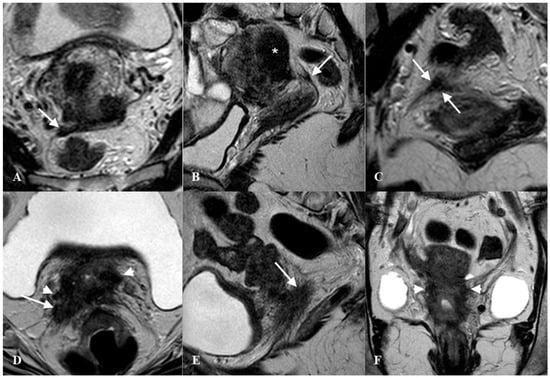

2.1. The Uterosacral Ligament

2.2. The Parametrium

2.3. The Paracervix

3. What Ultrasound Should Investigate and Detect